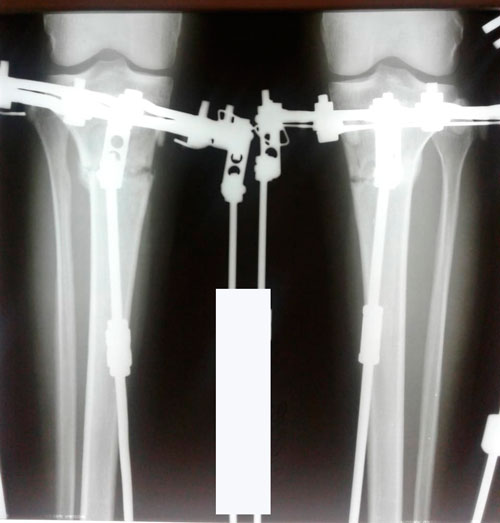

23 день после операции.

Вот в чем суть, щадящей и малотравматичной методики доктора Онипко.

Дата операции 01.06.2018г.

Дата снятия аппаратов 29.08.2018г.

Срок сращения 88 дней.